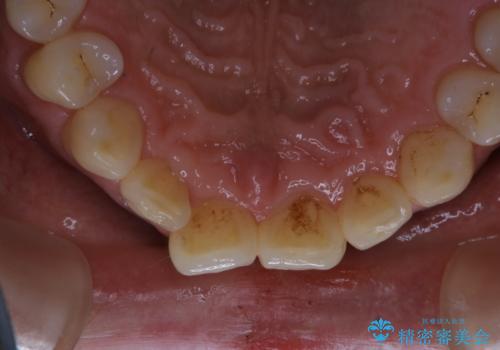

- 毎日コーヒーを飲むため、歯の着色がとっても気になるとのことでした。歯科でのクリーニングは2.3年ぶりのため全体的にきれいにしてほしいとのことでした。

PMTC60分コースを行いました。

プラークが放置されると、そこで歯周病菌が繁殖し始めます。よって歯肉に炎症が生じ、歯周病に引き金となります。

PMTC(保険外治療)は、毎日の歯磨きで落としきれない汚れや、コーヒ、紅茶・タバコのヤニなどの着色も除去します。目には見えない歯と歯の間・歯肉の境目・インビザライン中はアタッチメント周囲などに残っているプラーク(歯垢)もしっかり取り除きます。PMTCでは専門的な機械や材料を使用して、徹底的に汚れを除去するため、虫歯・歯周病・口臭予防などにつながります。